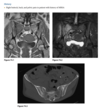

Anteroposterior view of the left foot

(Fig. 2.20.1) demonstrates vascular calcification,

soft-tissue swelling, lateral subluxation of the sec-

ond through the fifth metatarsals in relation to the

cuneiforms, and early destructive changes at the

tarsal-metatarsal joints. Notice the disruption of

the normal parallel alignment of the medial aspect

of the second cuneiform with the medial aspect of

the second metatarsal base (arrow).

Lisfranc fracture-dislocation, homolat-

eral type

On imaging, the Lisfranc

fracture-dislocation is seen as dorsal and lateral dis-

location of the metatarsal bases in relation to the cu-

neiforms. It is the most common dislocation in the

foot.

There are two distinct forms of the Lisfranc

fracture-dislocation: homolateral and divergent. In

the homolateral type, all metatarsals are dislocated

laterally in relation to the cuneiforms.

In the divergent type, there is lateral displacement of

the second through the fifth metatarsals and medial

or dorsal shift of the first metatarsal.

The characteristic radio-

graphic changes include soft-tissue swelling, vascular

calcification, bone destruction and fragmentation,

multiple fractures, and soft-tissue ossific debris from

the destructive changes

MR imaging can be useful in detecting bone marrow

edema, subcutaneous abscess, and sinus tracts